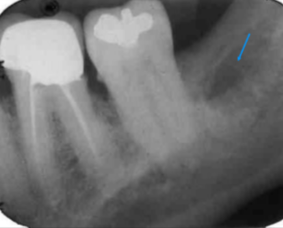

vertical bone loss

seen on radiographs as a non parallel line of bone loss

bone loss with furcation involvment

first sign of vertical bone loss

PDL space widens towards the crest

first radiographic sign of furcation involvement

pdl widening at furcation

vertical bone loss M/D of #2